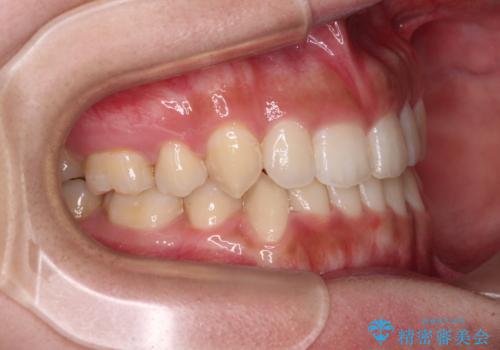

著しい八重歯が気になる インビザラインでの矯正治療

- 顕著な八重歯が気になるとのことで来院された患者様です。

インビザラインでの治療を希望されましたが、インビザライン単独では困難と判断されたため、補助装置や一部ワイヤー装置を用いて行うこととしました。

叢生が強いため、上下左右第一小臼歯4本を抜歯することとしました。